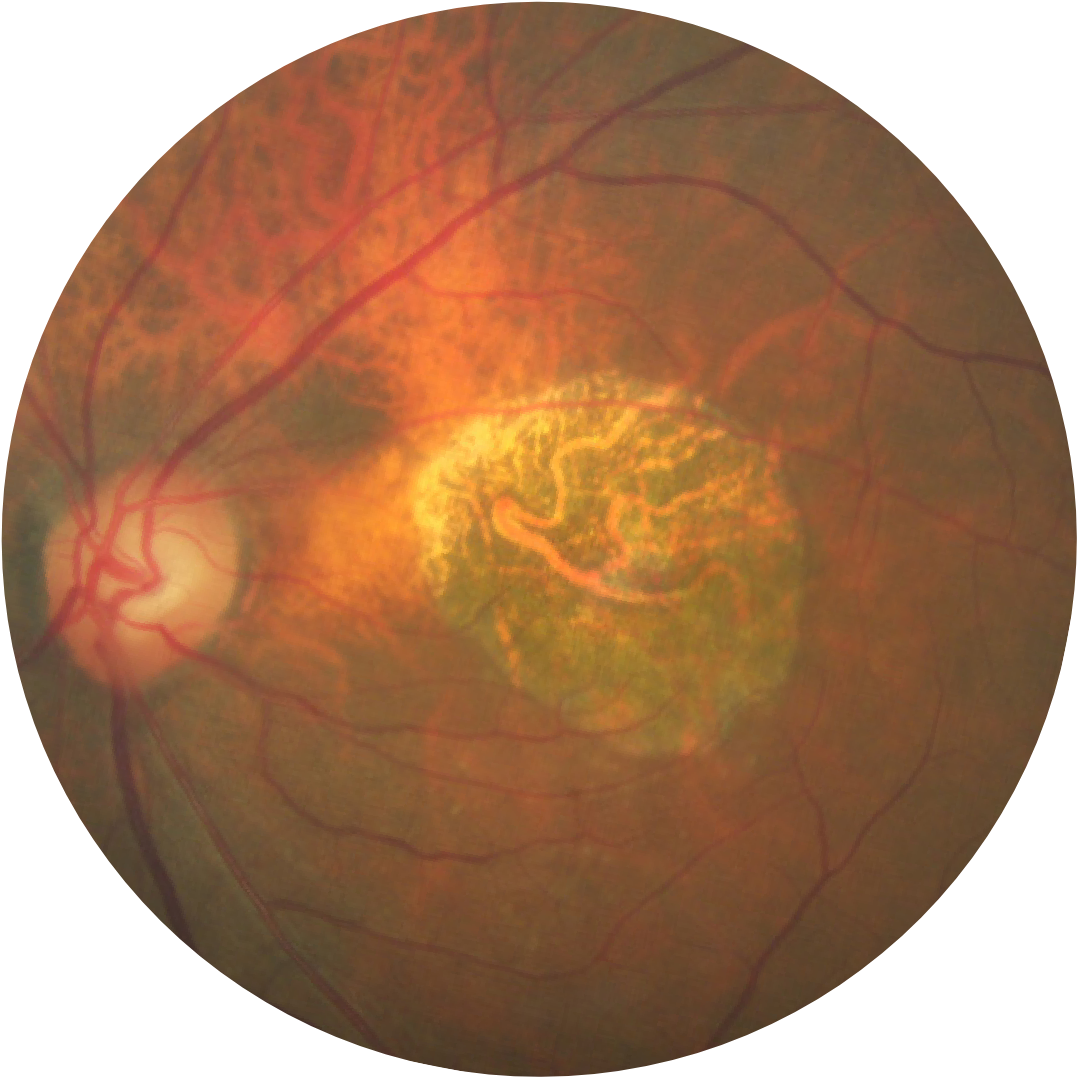

Fundusfotografie eines Auges mit Geographischer Atrophie

Die Geographische Atrophie ist durch einen progressiven und irreversiblen Verlust der Photorezeptoren, des retinalen Pigmentepithels (RPE) und der darunterliegenden Choriokapillaris gekennzeichnet.1,2

Atrophieregionen beginnen typischerweise außerhalb der Fovea und dehnen sich bis in die Fovea aus, was im Laufe der Zeit zu einem dauerhaften Verlust des Sehvermögens führt.1

Baseline Jahr 1

BCVA 20/63+, GA-Fläche 5,18 mm2

Baseline Jahr 2

BCVA 20/80-2, GA-Fläche 10,39 mm2

Baseline Jahr 5

BCVA 20/200, GA-Fläche 18,58 mm2

Das Läsionswachstum kann zu einer Verschlechterung der Sehkraft führen.2,16,17

Die Sehschärfe korreliert nicht stark mit dem Wachstum der Läsionen. Das funktionelle Sehvermögen nimmt mit dem Wachstum der Läsionen ab.15

BCVA = Bestkorrigierte Sehschärfe